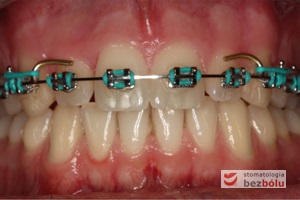

Młody 28-letni, pogodny, stale uśmiechnięty pacjent zgłosił się celem korekcji wad zębowych ograniczających pełną ekspresję uśmiechu. Głównym problemem był dodatkowy siekacz boczny (dwójka) po stronie prawej w łuku górnym. Dodatkowy ząb spowodował stłoczenia pozostałych zębów w łuku górnym oraz przesunięcie linii pośrodkowej. Obliczenia dostępnego miejsca dla siekacza bocznego wpłynęły na wybór zęba przeznaczonego do ekstrakcji. Usunięto dwójkę ustawioną dowargowo, zaś jej „siostrę bliźniaczkę” skierowaną w stronę podniebienia wprowadzono do łuku zębowego w drodze leczenia ortodontycznego. Problemem było szczelne zamknięcie szpary poekstrakcyjnej z powodu nadmiaru miejsca w kości. Wyrównano linię pośrodkową. Leczenie przeprowadzono jednym łukiem ortodontycznym górnym, dolny łuk zębowy nie wymagał założenia aparatu. Po zdjęciu zamków korekcję detali przeprowadzono z użyciem pozycjonera wykonanego w technice termoformingu. Stabilizację efektów leczenia zapewnił stały retainer klejony do powierzchni podniebiennych siekaczy górnych.